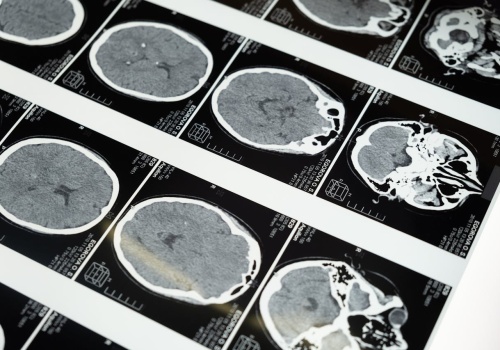

Robotyczna angiografia mózgu może skracać czas zabiegu i zachować pełne bezpieczeństwo – pokazuje nowe badanie. Artykuł Robot przyspiesza angiografię – badanie pokazuje krótszy czas zabiegu i 100% skuteczności pochodzi z serwisu Alert Medyczny.